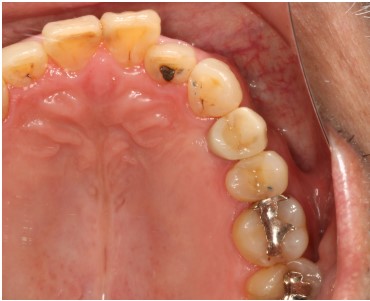

2024.08.1750代女性「前歯がぐらぐらして痛みがある」ブリッジとインプラントで揺れることなくお口全体で物を噛めるようになった症例